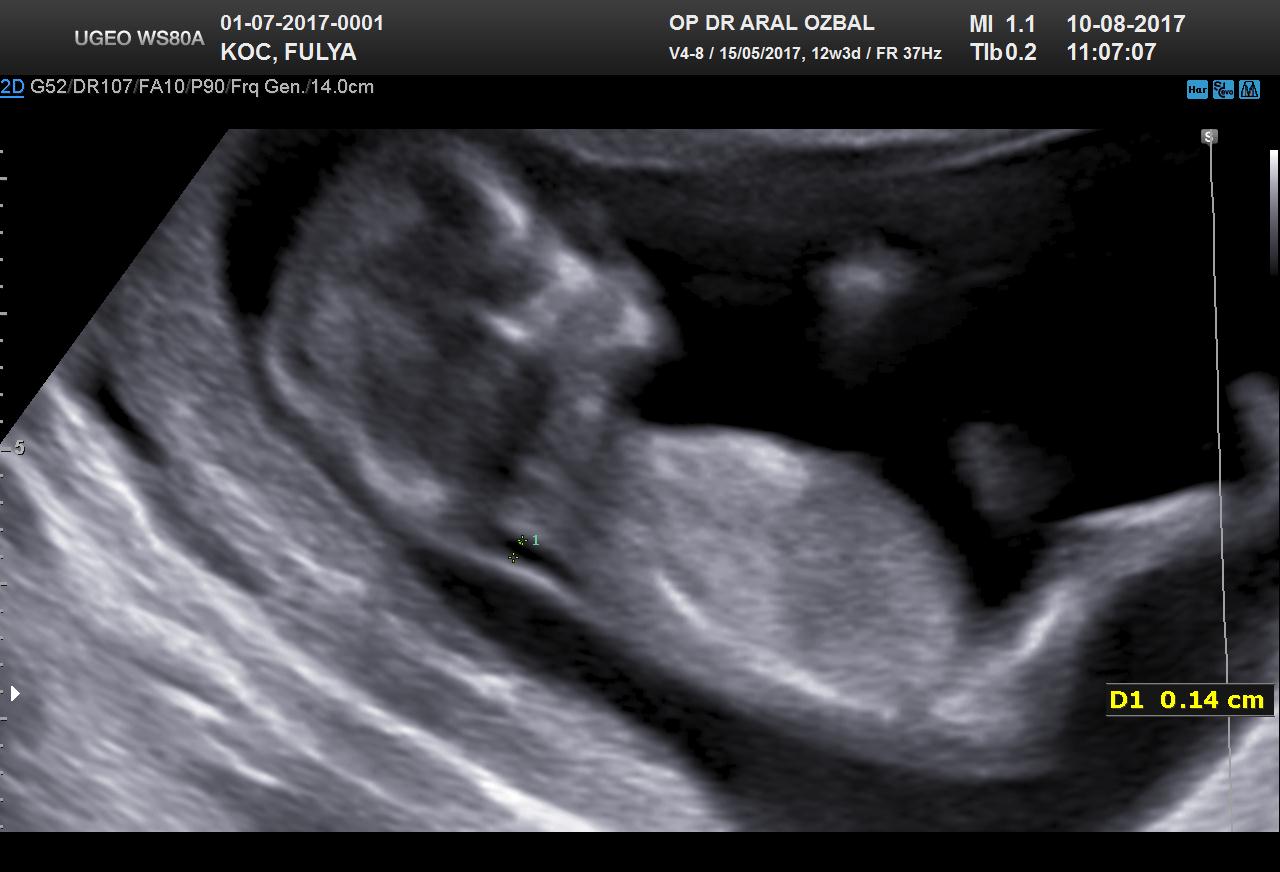

G Gülbaharr@86 Yeni Üye Üye 15 Ağustos 2017 #30 Lütfen cinsiyet yorumu alabilirmiyim...Birkaç foto yükledim ama umarım görebilirsiniz... Ekli dosyalar 20170727145738_740.jpg 92,5 KB · Görüntüleme: 910 20170810111903_604.jpg 84 KB · Görüntüleme: 932 20170810111903_100.jpg 117,4 KB · Görüntüleme: 951